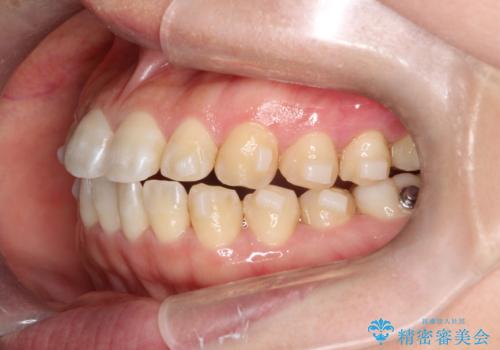

【インビザライン】前歯のすきまを閉じたい

- 前歯の隙間を主訴に来院されました。

インビザライン にて治療を行い、歯並びを改善することができました。